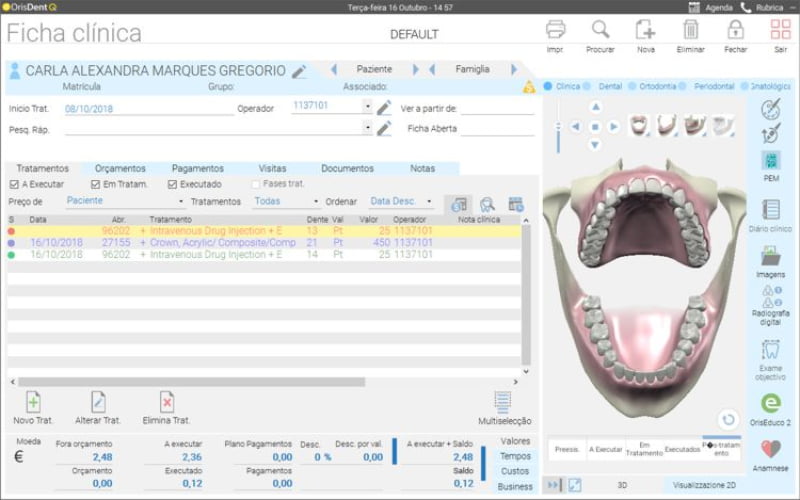

Chama-se OrisDent Q e é a nova geração de software para gestão de clínicas dentárias da OrisLine. De acordo com a empresa, o novo software permite “organizar as questões fiscais, cumprir os regulamentos mais recentes e integrar com os sistemas mais avançados”.

“O OrisDent Q aproveita a experiência anterior do OrisDent evo, desenvolvido com tecnologia de ponta, funções avançadas e design moderno, foi desenvolvido para gerir e processar dados da clínica com segurança e estabilidade, tanto num único computador ou em redes mais complexas”, acrescenta ainda a OrisLine.

“Com o OrisDent Q pode manter a agenda sempre aberta num segundo monitor e pode apresentar tratamentos com o novo visualizador 3D. Possui ferramentas avançadas de análise que permitem calcular o retorno do investimento em campanhas de marketing realizadas pela clínica e a margem sobre os orçamentos e tratamentos”, conclui a empresa.